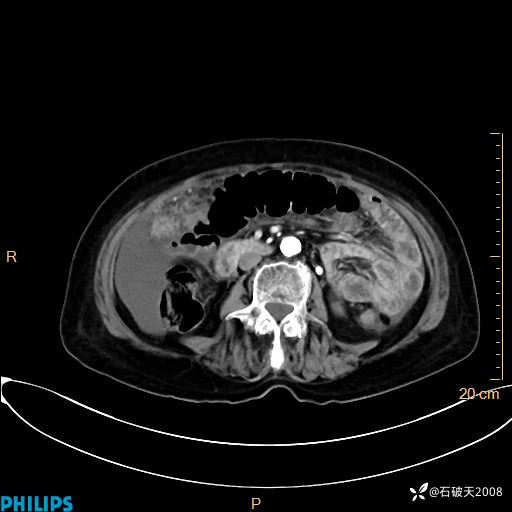

动脉期